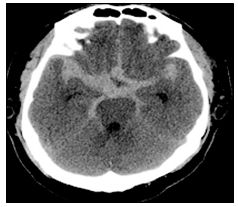

40대 여자가 갑자기 벼락 치듯 심한 두통과 의식저하로 응급실에 내원하였다. 뇌 CT 영상이 다음과 같을 때 진단으로 옳은 것은?